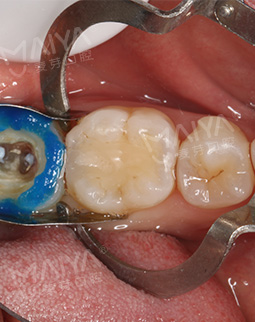

2018年5月 矫牙的宝宝们也要时刻注意自己口内状况

复诊的时候到了,戴着我的牙套去补牙了,说起这个烂牙也是因为咬合不佳造成细菌滋生的,身为医护,其实自己的牙齿应该很注意才对,都是之前抱有侥幸的心理,所以提醒各位想矫牙的同学,要早点看牙医!不过烂牙当然不影响我矫正,补牙的是另一位全科医师,也很细心,用的是3m树脂的材料,真的和真牙颜色一样~